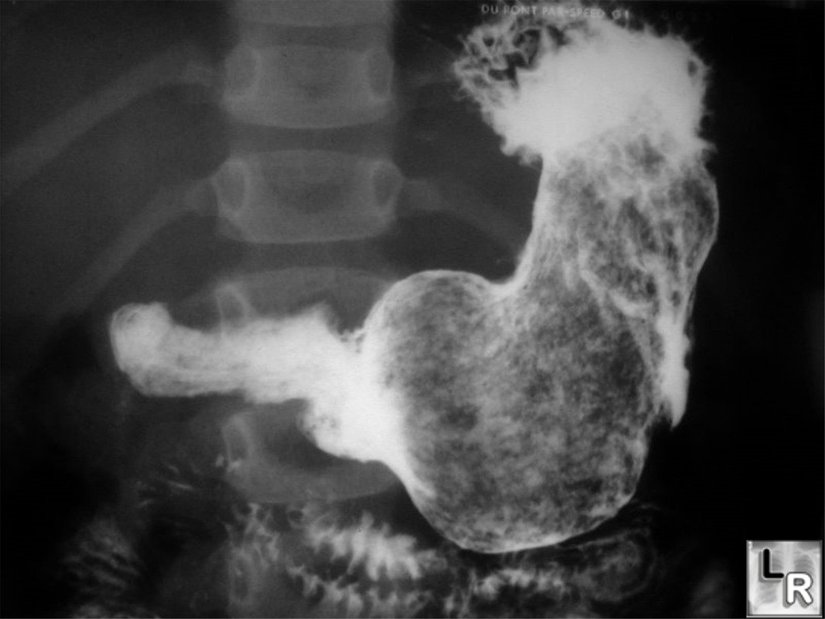

Trikofajik bireylerin midelerinde genellikle kıllar parçalanır veya bütün olarak sindirim kanalını kat ederek dışkıyla dışarı atılır. Fakat eğer ki bu davranış çok sık tekrarlanıyorsa, çok sayıda kıl birbirine yapışarak yumaklar oluştururlar. Bu kıllar, bağırsaklarda yumaklar olarak biriktiğinde, dahiyane bir şekilde isimlendirilmiş "Rapunzel Sendromu" görülebilir. Bu sendroma sahip 18 yaşındaki bir gencin bağırsaklarından 4.5 kilogramlık kıl yumağı çıkarılmıştır. Bu yumaklar, midenin veya bağırsakların şeklini alıp onları tıkayacak kadar fazla miktarda birikebilir.

Bu hastalığın tedavisi de diğer dürtü kontrol bozukluklarının tedavileriyle aynıdır: psikolojik tedavi görülür. Ayrıca trikofajinin kimyasal dengesizliklik sonucu da tetiklenebildiği düşünülmektedir. Bu nedenle anti-depresanlar ve psikoterapi bir arada sürdürülür. Aşağıda, bazı trikofaji vakalarında çıkarılan kıllar, nasıl göründükleri, ne büyüklükte yumaklar oluşturdukları görülmektedir.